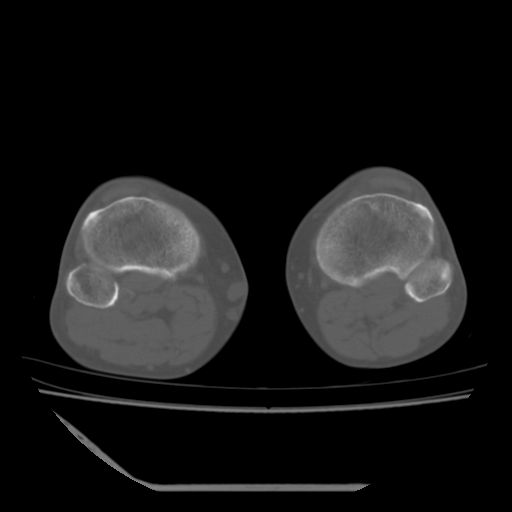

标题: CT13225:老年男性,左膝关节疼痛数月;请各位老师讨论。 [打印本页]

标题: CT13225:老年男性,左膝关节疼痛数月;请各位老师讨论。

骨质增生,骨性关节面硬化,关节积液,考虑退行性骨关节病

关节腔内少量积液,关节面退变。

双膝退变

骨质增生,骨性关节面硬化,关节间隙失常,关节积液,考虑退行性骨关节病.

这个病例诊断:退行性骨关节炎